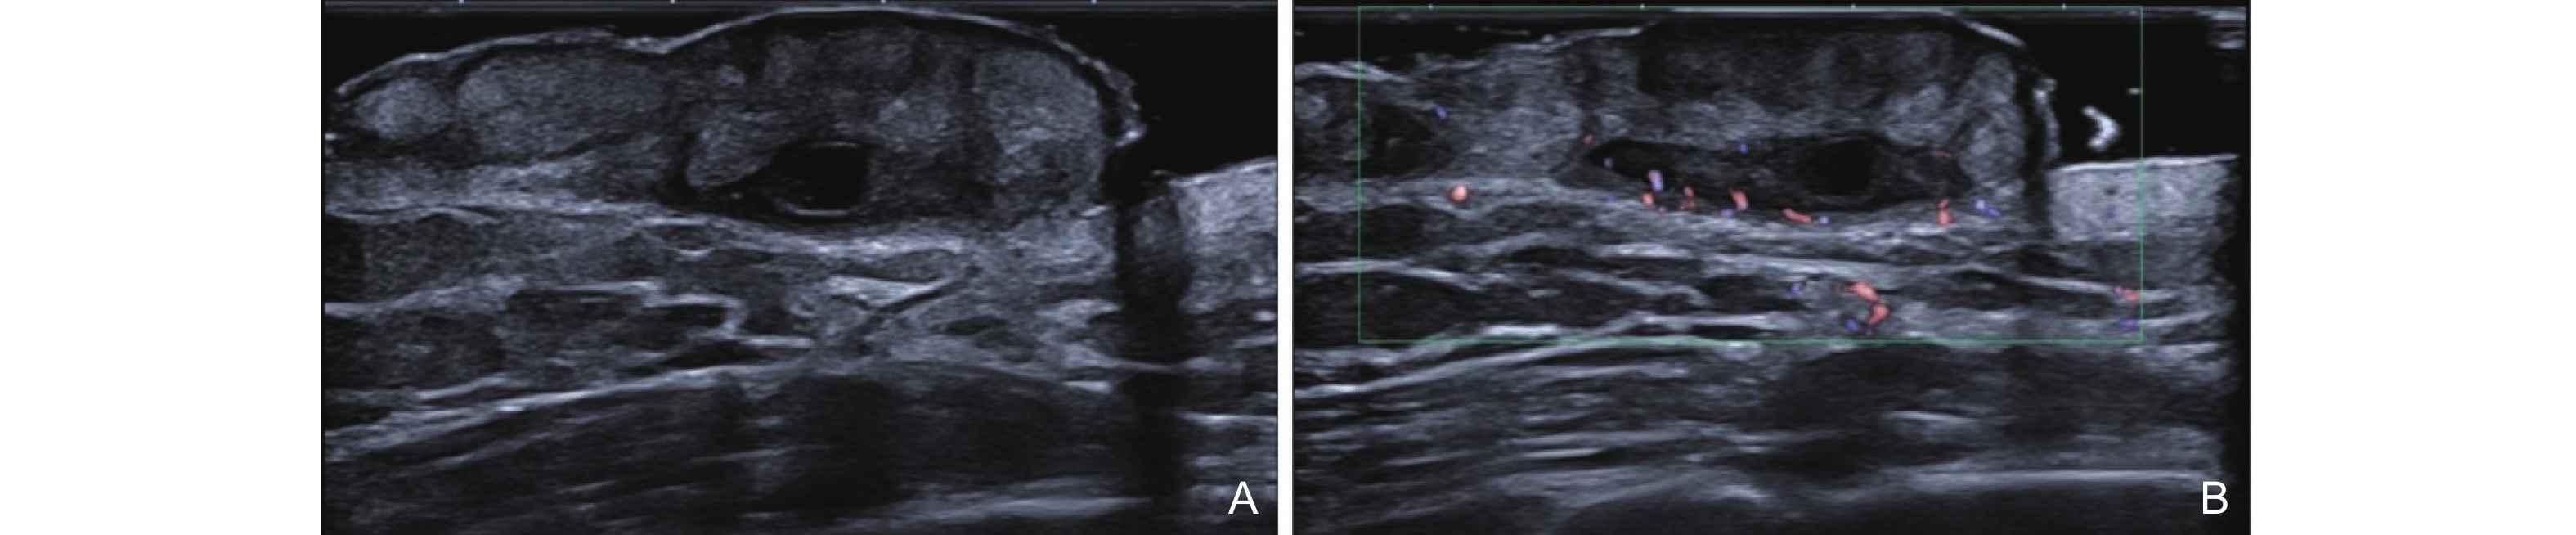

Figure 3

Clinical [47] and ultrasound manifestations of port-wine stains. (A) Pink type of PWS; (B) Purple type of PWS; (C) Thickening type of PWS; (D) Comparison of gray-scale ultrasound between the PWS lesion and the healthy side; (E) The blood flow signal at the lesion site of PWS increases."

| [47] | Xiang Xi , Zhang Lingyan , Zhong Lin , Gao Yi , Qiu Li . Multimodal ultrasound manifestations of port-wine stains and their application in efficacy assessment of photodynamic therapy. Chinese Journal of Dermatology 2024; 57: 801-806 |